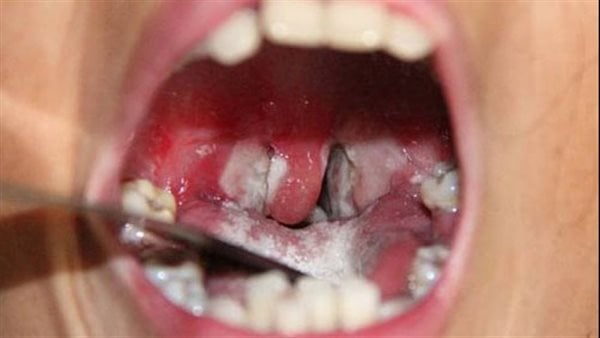

تسجيل 90 إصابة بالدفتيريا بولاية لعصابة

قال وزارة الصحة إن مجموع حالات المشتبه بإصابتها بوباء الدفتيريا “الخناق” في ولاية العصابة، بلغ 90 حالة، توفيت منها 8، وشفيت 62 حالة، وما زالت 20 حالة تحت العلاج.